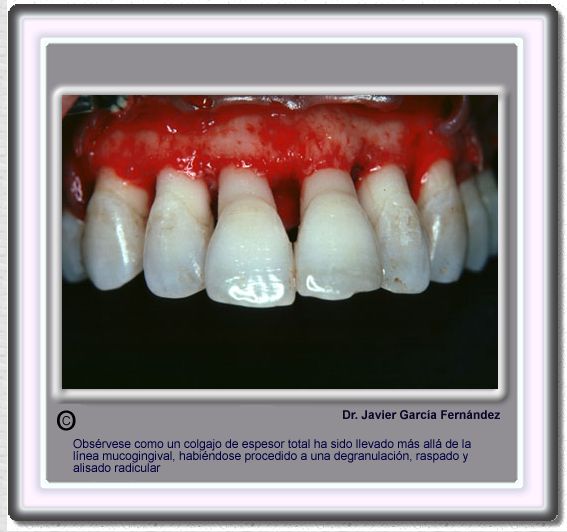

image 831